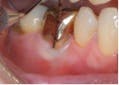

Most difficult of the endodontic-periodontal relationships to understand are the combined lesions. First, an untreated, long standing endodontic lesion may result in chronic, marginal periodontal breakdown. This is characterized by a non-vital pulp response, a deeply probing pocket, and the usual signs of periodontal disease such as plaque, calculus, and other indications of poor oral hygiene. In this case, the affected tooth requires both root canal threapy and localized periodontal treatment, such as scaling and root planing. Endodontic therapy alone may not resolve the existing pocket until the prognosis of periodontal resolution can be determined. Second, a periodontal pocket that has been left untreated, causing the resulting bone loss to expose the apical foramen to the oral environment, can lead to a “retrograde pulpitis” and subsequent necrosis of the pulp (Figures 4, 5, and 6).

Bacteria enter the root canal system through the apical foramen or lateral canals, requiring root canal therapy to remove the dead or dying pulp. Diagnostically, there may be a response to thermal stimulation, depending upon the extent of the pulpal breakdown, but root canal therapy is required nonetheless. The prognosis in this situation is strictly dependent upon the condition of the periodontium and the extent to which it responds to periodontal treatment (Figures 7, 8).